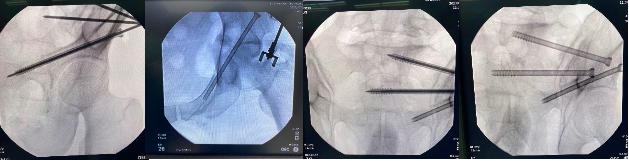

手术当天,骨科治疗组组长何罕亮副主任团队先采用我院先前引进的二代O臂机,现场拍摄患者的骨盆图像,上传至骨科机器人电脑中,经过机器人精密处理,患者的骨折三维图像直观地呈现在了所有人面前。随后,何主任根据图像,实时进行手术规划,选择最佳置钉通道。手术方案规划完毕后,手术机器人机械臂根据制定好的路线精准定位,将误差控制在1mm之内,医生不必切大切口,只需通过3个几毫米的切口便可将螺钉精准打入狭长的耻骨中,如此一来也不会损伤重要的血管神经组织。一旦通道确定,整个置钉过程不过短短几分钟,手术出血不足10ml,精准的置钉操作让医生不必担心需要反复调整而导致钉道松动。术后透视确认了螺钉位置准确无误,手术圆满成功,病人术后恢复满意。

机器人术中规划髋臼前柱螺钉&骨盆骶髂螺钉